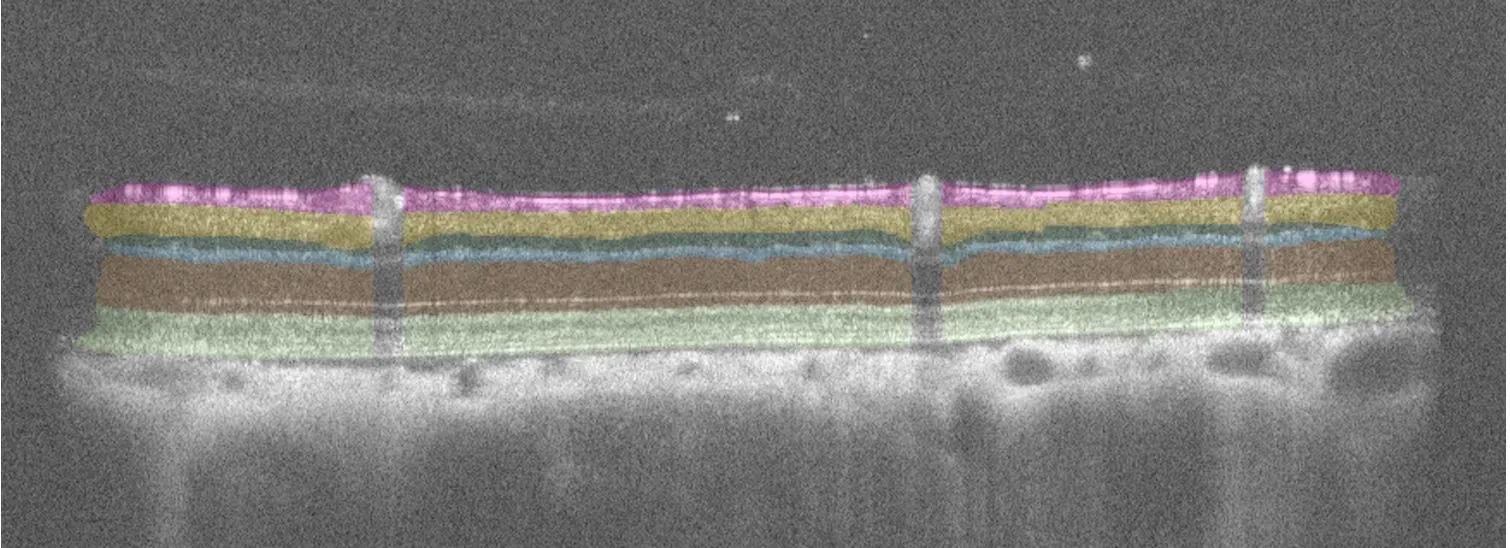

– Inner retinal thickness measurements (SD-OCT)

Controlled IOP elevation allows adjustable severity of injury, analyzed for functional and structural insights using SD-OCT, ERG, OMR and histology.